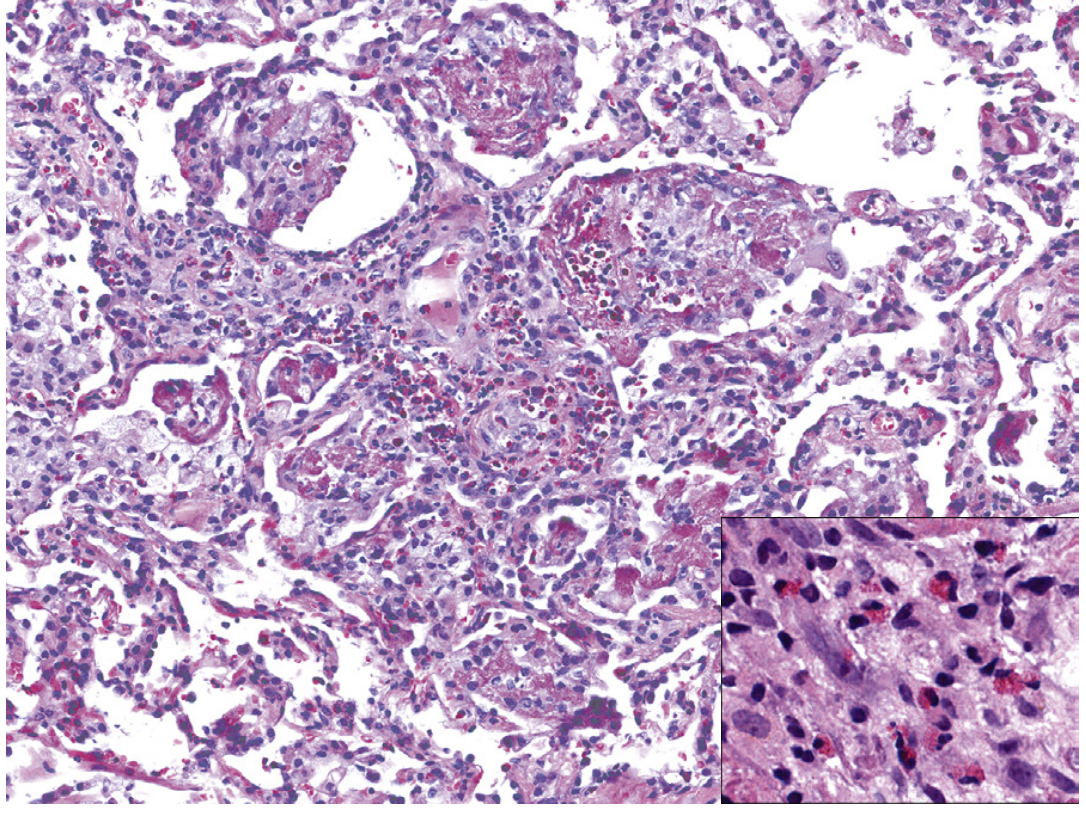

Histology of eosinophilic pneumonia showing eosinophils in fibrin-rich alveolar exudates

Eosinophilic pneumonia: dense eosinophilic infiltrates in fibrin-rich alveolar exudate (H&E ×200). Inset: eosinophils at high magnification (×400). — Murray & Nadel's Textbook of Respiratory Medicine

Light microscopy reveals:

• Prominent eosinophil infiltration in interstitium, alveolar spaces, and bronchial walls

• Diffuse alveolar damage (DAD) pattern with hyaline membranes — distinctive for AEP

• Type 2 pneumocyte hyperplasia

• Intra-alveolar fibrinous exudate

• Lymphocytic interstitial infiltration

• Granulomas, alveolar hemorrhage, and non-necrotic perivascular inflammation reported

• Basal lamina damage is unusual